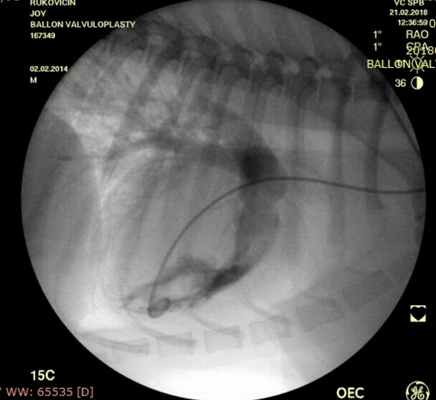

Показанием к оперативному лечению служит градиент систоличесокого давления на клапане легочной артерии свыше 50 мм рт.ст. При наличии дисплазии створок клапана — показана хирургическая коррекция порока, в остальных случаях возможно эндоваскулярное лечение. Операция выполняется в большинстве случаев под в/в анестезией, за исключением новорожденных, находящихся в критическом состоянии, у которых операция выполняется пол общим обезболиванием. Суть операции заключается в том, что после пункции бедренной вены в полость правого желудочка проводится и устанавливается катетер, далее проводник через клапан легочной артерии проводится в дистальные отделы легочной артерии. По проводнику в последующем проводится баллонный катетер и выполняется вальвулопластика. В настоящее время операция не сопровождается развитием летальных исходов и осложнений. Госпитальный период ограничен 3 днями.

Проведено: баллонная вальвулопластика клапана легочной артерии (Тип А). Баллон Cordis maxi 40х20 мм. Инфляция до 5 атм. 10 попыток.